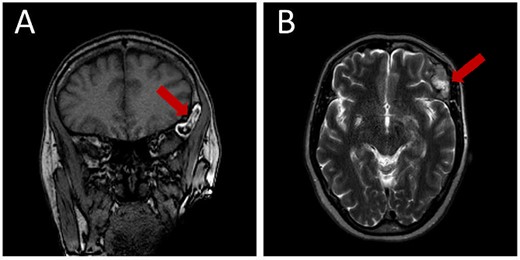

Prior diagnostic imaging included a computed tomography (CT) scan, revealing a hypodense lesion in the left fronto-zygomatic region (Fig. 1). Subsequent brain magnetic resonance imaging (MRI) showed a high-intensity lesion on T1-weighted images (T1WI) (Fig. 2A), and an iso-to-hyperintense lesion on T2-weighted images (T2WI) (Fig. 2B).

Pre-operative brain MRI exhibiting: (A) a high-intensity lesion in the left fronto-zygomatic region on coronal T1-weighted images (T1WI), and (B) Axial T2-weighted images (T2WI) depicting variable signal intensity ranging from iso- to hyperintense.